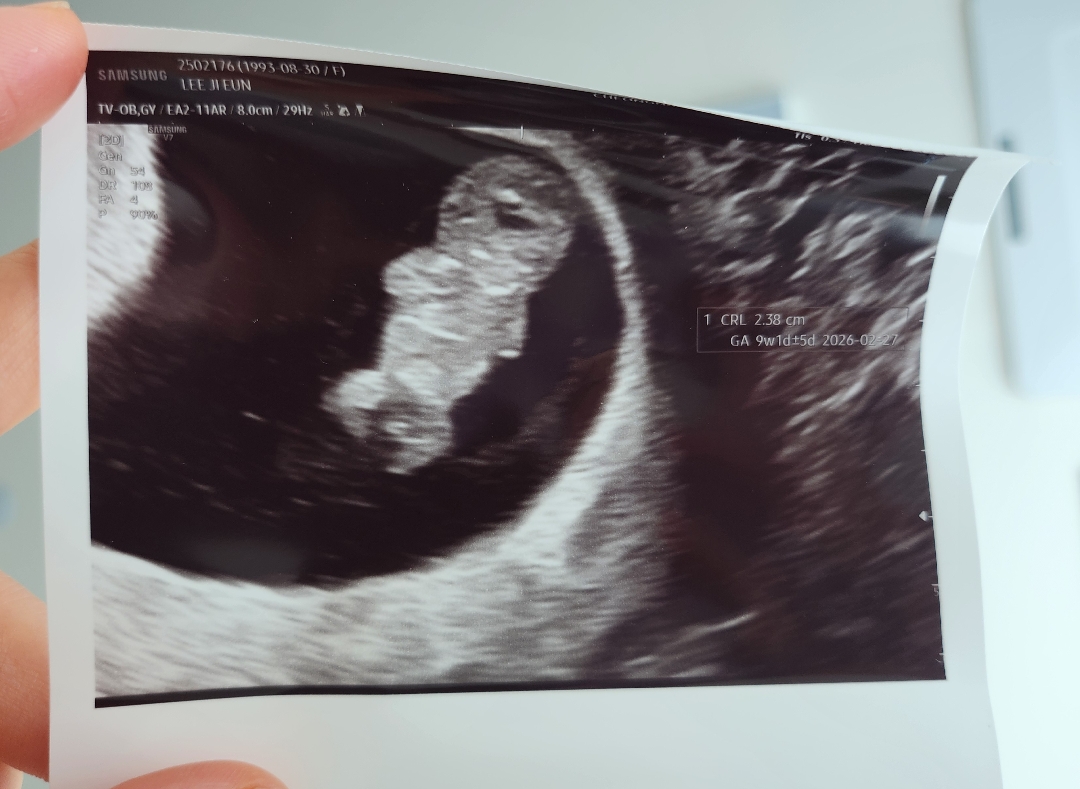

9주0일 젤리곰 보고 왔어요!

어제 드디어 9주0일차 젤리곰 보고 왔어요! 심장소리도 좋고 사람이 되어서 꼬물꼬물 움직이는것도 너무 신기하고 귀엽더라구요!! 근데 8주차에 젤리곰이 잘 보인다던데 9주차여서 그런가 제 눈에만 통닭같이 보이는걸까요!??🤣🤣